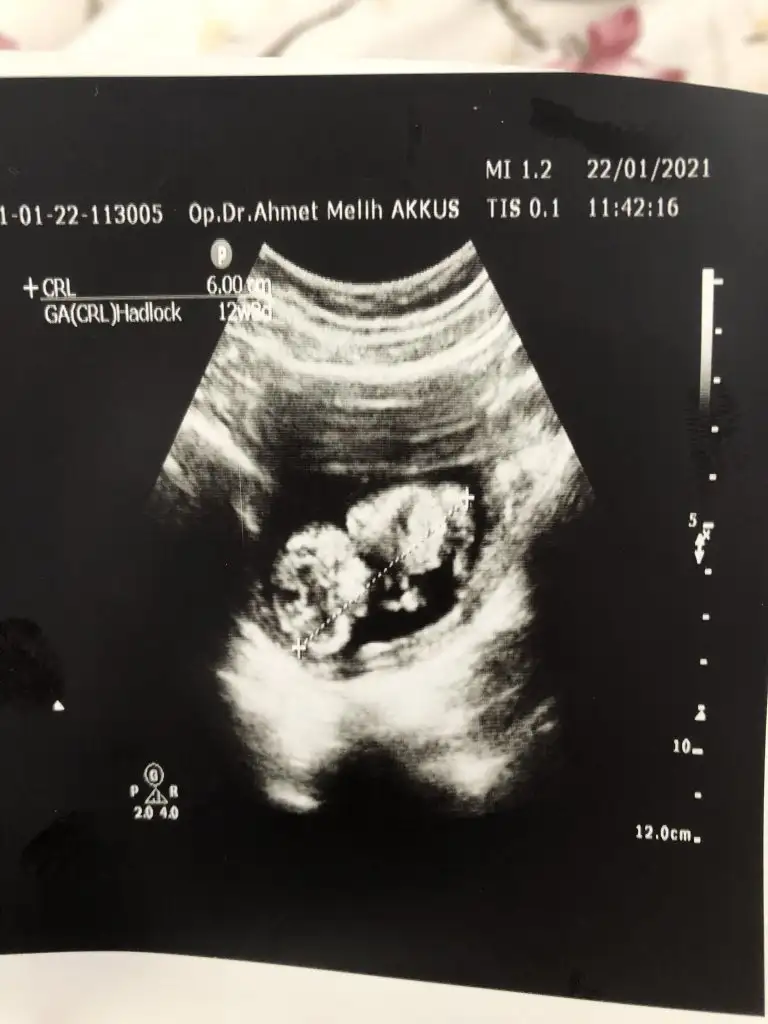

Ikra meyra Ikra meyra canım benimkine de bakabilir misin? 12+2

Eklentiler

• A85EC690-102B-49C7-B9EA-10869B2BEC36.webp

A85EC690-102B-49C7-B9EA-10869B2BEC36.webp

32,6 KB · Görüntüleme: 78

• B9CAB7C7-D655-4766-BFC8-F19DFF013044.webp

B9CAB7C7-D655-4766-BFC8-F19DFF013044.webp

29,9 KB · Görüntüleme: 81